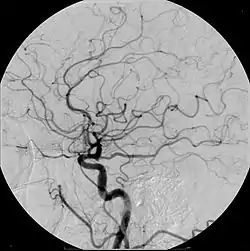

Ангіогра́фія (грец. αγγειον — судина і γραφω — пишу) — метод спеціального рентгенологічного дослідження кровоносних судин різних органів шляхом введення в артеріальну чи венозну систему речовин, які дають різку тінь в рентгенівських знімках. Ангіографія без контрастної речовини також можлива за допомогою МРТ.

- Дигітальна субтракційна ангіографія (DSA)

- Церебральна ангіографія - розроблена в 1927 р. португальським лікарем Антоніо Егасом Монізом та його колегою Педро Мануелем де Альмейдою Лімою, її було легше використовувати, коли на початку 1950-х було винайдено катетер Зельдінгера. [1]